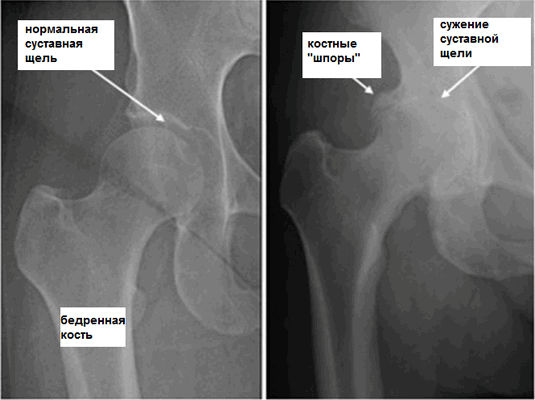

Коксартроз

Причиной развития такого заболевания является изменения структуры хрящевой ткани, нарушение питания и кровоснабжения тканей. Спровоцировать проблему может аномальное строение скелета, нарушение обменных процессов в организме, слишком большая масса тела. Симптоматика при этом такова: изначально появляется стартовая боль, которая имеет умеренную интенсивность. Однако со временем дискомфорт и неприятные ощущения усиливаются.

Если на 1 стадии сначала они появляются только при движении, то с развитием заболевания болевой синдром не проходит даже во время покоя. На второй и третьей стадиях развития патологии боль не исчезает даже ночью. Объем движения уменьшается с каждым днем. Естественно, необходимо обязательно проводить лечение этой болезни. Если она уже запущена, то на 4 стадии патологии придется делать операцию. Дело в том, что болезнь способствует деформации тазобедренного сустава. При данном заболевании болевые ощущения могут появляться даже в боку, паху и колене. Мышцы при коксартрозе сильно напрягаются, больной начинает хромать.